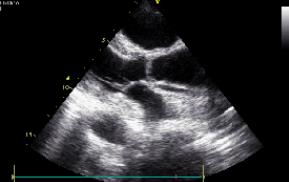

左心室增大

心室肥大

查体:体温37.5°C,呼吸22次/min,血压125/90mmHg,贫血貌,心界左下扩大,心率107次/min,律齐,奔马律,肝脏肋下3cm,脾肋下未及,双下肢无水肿。 辅助检查:血白细胞6.21x10^9/L,中性61.1%,血红蛋白92g/L,24h尿蛋白定量3.42g,肌钙蛋白I0.36μg/L,抗核抗体(-),抗双链DNA抗体(-),超声心动图示左心室增大,室壁运动普遍减低,收缩功能重度减低,左心室射血分数35%。